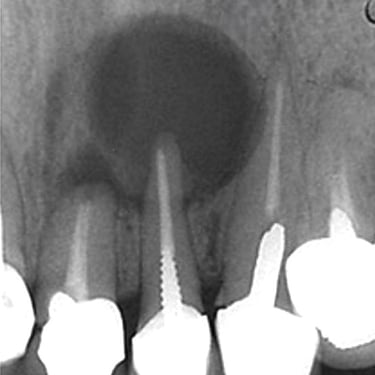

Quiste Periapical

Un quiste periapical es una cavidad llena de líquido en la punta de la raíz del diente, generalmente resultado de una infección crónica.

Los pacientes pueden notar una hinchazón sin dolor en la encía.

El tratamiento incluye el tratamiento de conducto y, a veces, la extirpación quirúrgica del quiste. Si no se trata, el quiste puede crecer y causar complicaciones.